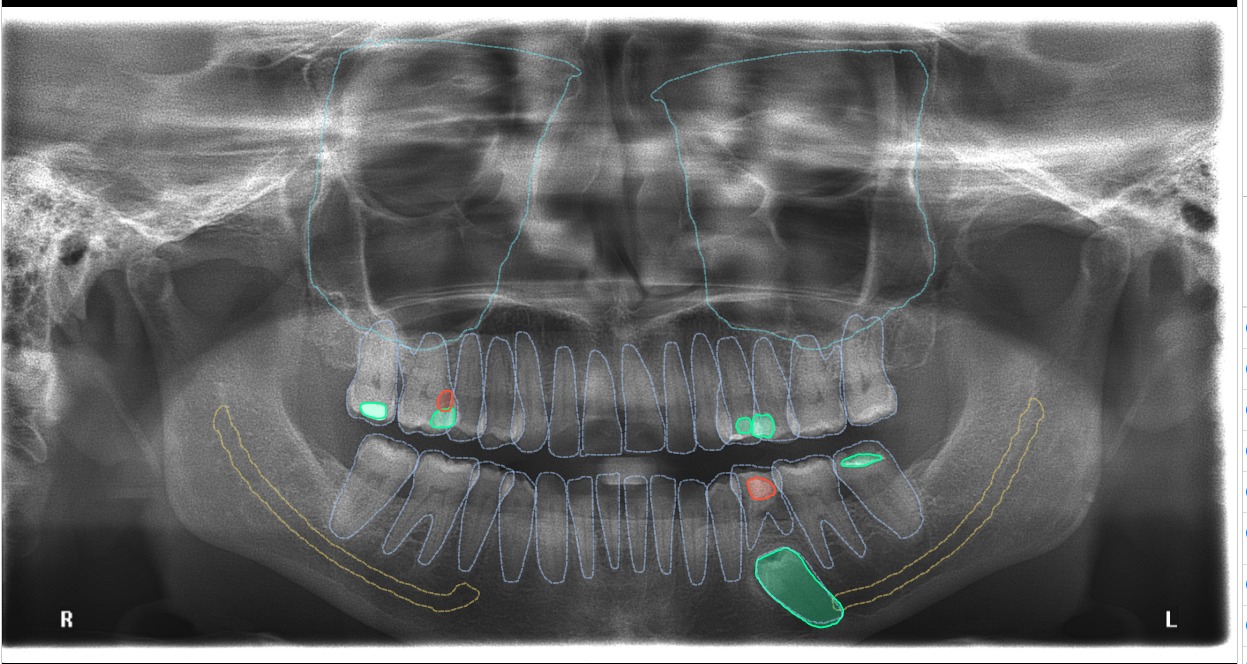

Orthopantomogram (OPG): A jaw-sized x-ray showing all teeth, upper and lower jaw bones, jaw joints, and maxillary sinuses.

• Our clinics are equipped with AI-guided solutions that can scan the OPG and detect abnormalities in approximately 5 seconds, helping dentists promptly diagnose oral conditions.

OPG After AI-Guided Detection